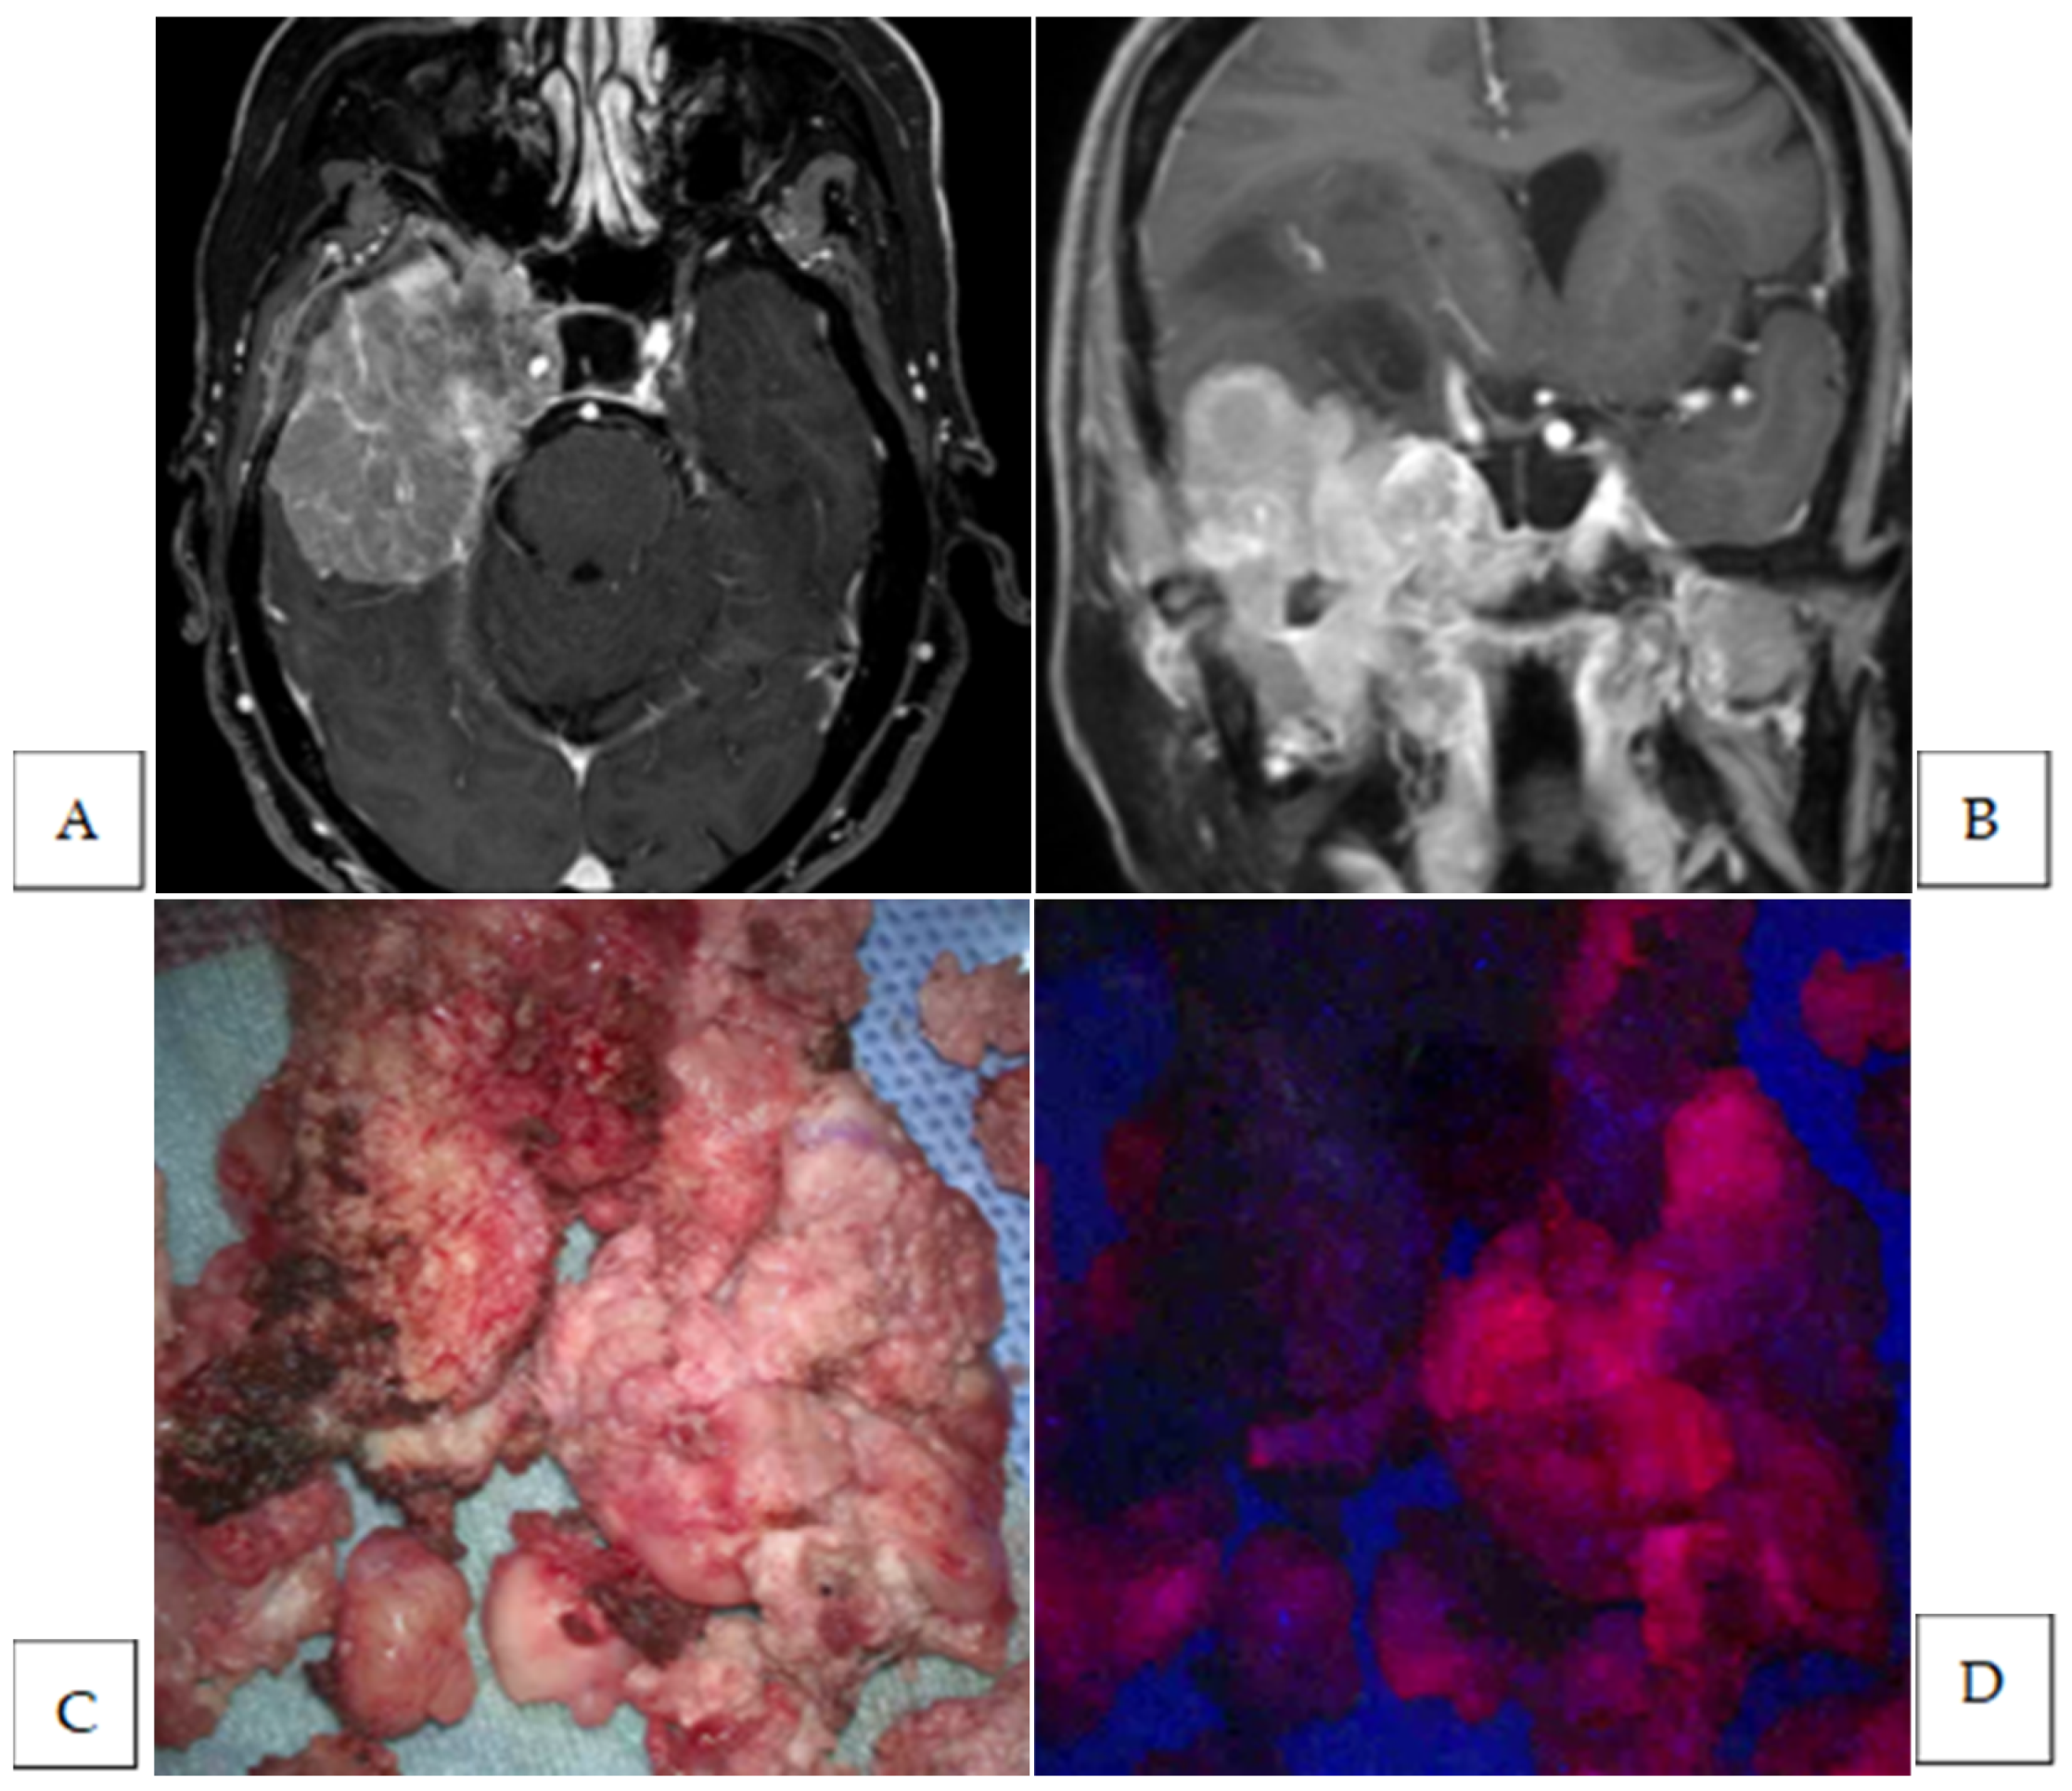

| 7 | middle fossa | transitional | Strong | yes | yes | brain | 1 | no |

| dura | 1 | yes | ||||||

| bone | 2 | yes | ||||||

| 8 | convexity | meningothelial | Strong | no | no | |||

| 9 | convexity | meningothelial | Strong | yes | yes | brain | 1 | no |

| 10 | sphenoid ridge | anaplastic | Strong | yes | yes | dura | 2 | NA |